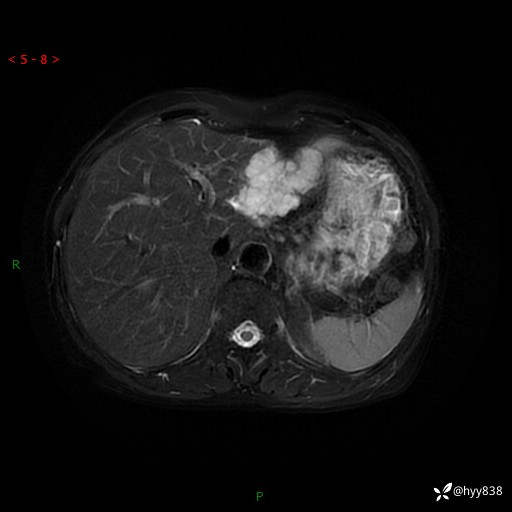

肝脏MRI平扫(同反相位)

T2WIfs+DWI

增强(动脉期+静脉期+延迟期)